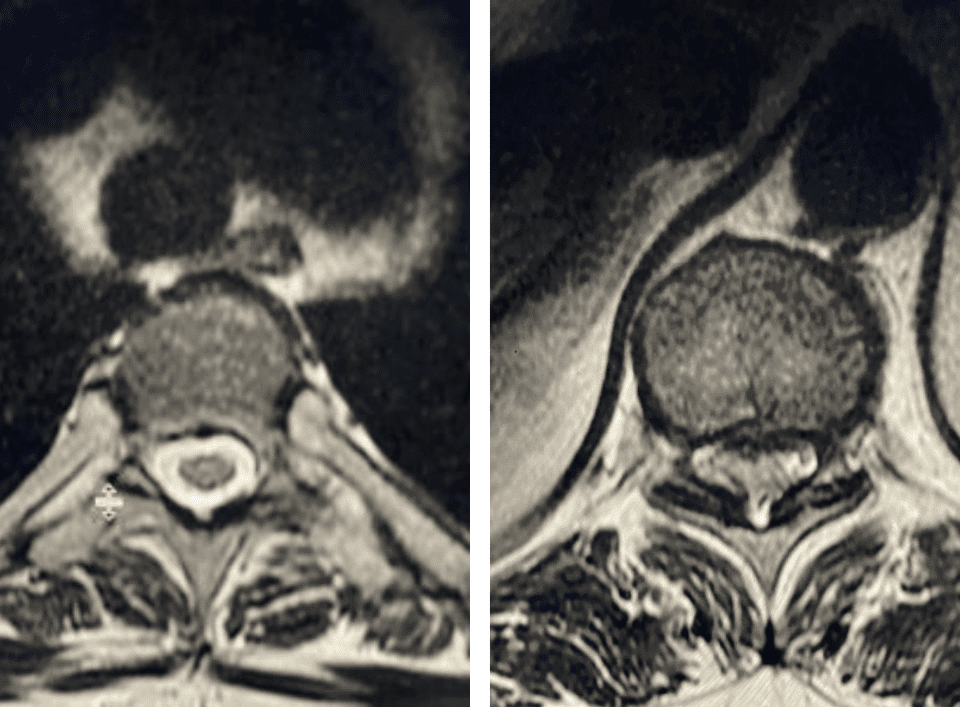

People are obsessed with cysts! When you think about it, the body likes to form cysts. Why does this happen? Cysts can form just about anywhere […]

The spinal synovial cyst is one of the most interesting expressions of spinal instability. They emanate from the synovial lining of a degenerated facet joint that […]